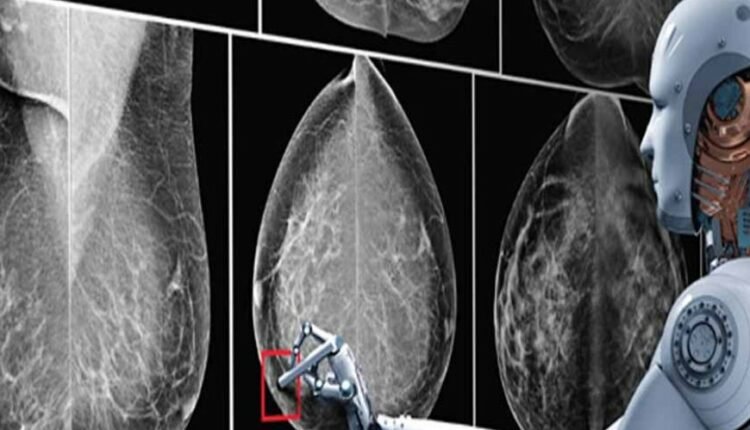

हाल ही में अमेरिका की Duke University के रिसर्चर ने एक New AI डेवलप किया है। इसके रिसर्चर ने दावा किया है कि, AI ब्रेस्ट कैंसर को उसके डेवलप होने से लगभग पांच साल पहले ही डिटेक्ट कर सकता है। अब आनंद महिंद्रा ने साइंस न्यूज नाम के हैंडल पर की गई पोस्ट को रिपोस्ट किया है। उन्होंने इस पर लिखा है कि यह बहुत काम का साबित हो सकता है।

कैंसर का पता लगाने के लिए फिलहाल Biopsies, Microscopic Histological एग्जामिनेशन मेथड का इस्तेमाल किया जाता है। इसके अलावा इमेजिंग टेक्नोलॉजी जैसे MRI, CT स्कैन और PET स्कैन हैं। अब रिसर्चर्स ने दावा किया है कि AI की मदद से एक्यूरेसी के साथ कैंसर की रिपोर्ट दे सकता है।

हाल ही में अमेरिका बेस्ड Duke University के रिसर्चर ने एक New AI डेवलप किया है. यह AI मॉडल कैंसर डेवलप होने से करीब 5 साल पहले कैंसर को बता देगा. ये दावा रिसर्चर ने किया है.

कैंसर का पता लगाने के लिए, जो ट्रेडिशनल तरीका है, वो Biopsies, Microscopic Histological एग्जामिनेशन है. इसके अलावा इमेजिंग टेक्नोलॉजी जैसे MRI, CT और PET Scans हैं. वहीं, AI सिर्फ मेडिकल इमेज को एनालाइज करके ज्यादा बेहतर एक्युरेसी के साथ कैंसर की रिपोर्ट दे सकता है, जो दावा रिसर्चर ने किया है.